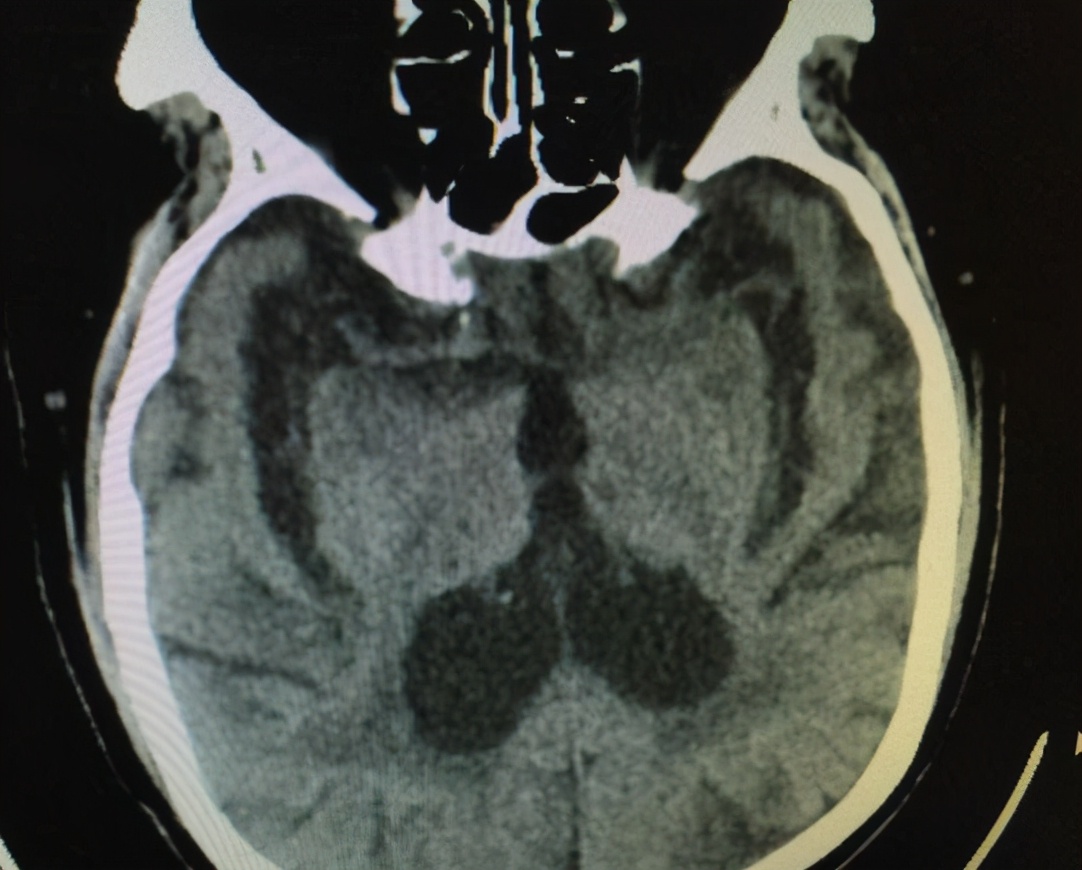

CT检查可直接观察到活体脑组织的结构,从而直观地发现脑组织是否发生了体积减小、脑室增大,帮助判断患者的脑萎缩程度。通过检查结果的研究统计普遍认为,50岁以上人群随年龄增长会出现普遍性脑萎缩,但多为轻度。男性30~40岁阶段较同龄女性发生大脑萎缩的速率更高,可能与内分泌激素差异有关。随着年龄增长,70岁以后人群脑萎缩则更为显著,但总体而言生理性脑萎缩仍属正常范围内。

根据病史、症状、影像学检查诊断脑萎缩并不困难,但要与其他类似表现的疾病进行鉴别。在排除了如肿瘤、梗塞等严重病理因素后,采取正确的措施防治脑萎缩是有一定效果的。